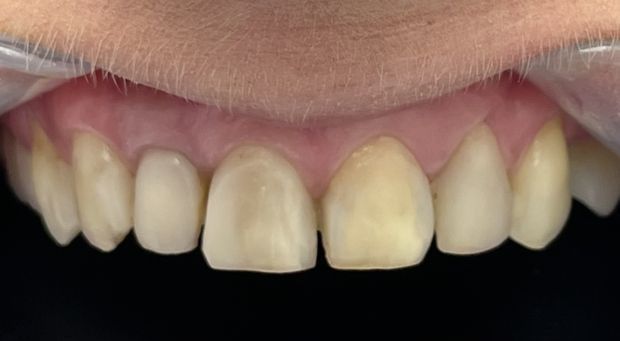

Licówki pełnoceramiczna wykonane cyfrowo w systemie CAD/CAM w przypadkach, kiedy poprawiamy estetykę – kształt i kolor zębów.